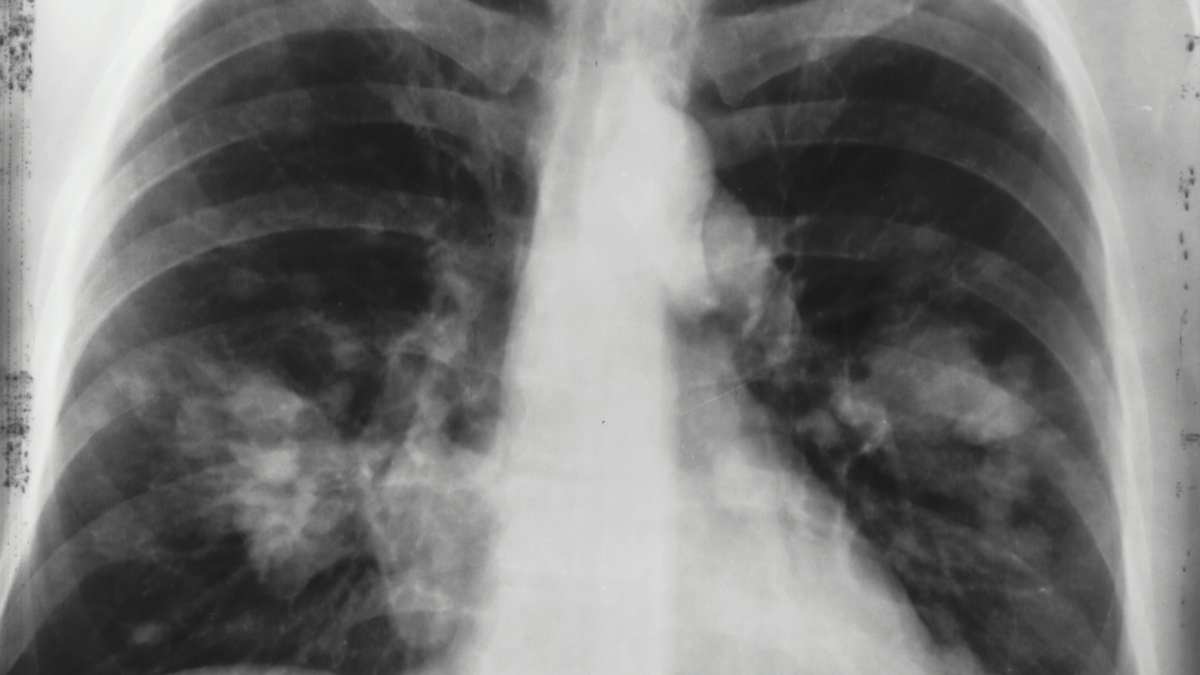

The Department of Health (DOH) has raised alarm over the deadly link between tuberculosis (TB) and human immunodeficiency virus (HIV), stressing that one in every five deaths among people living with HIV (PLHIV) is caused by TB.

In a statement on Sunday, the DOH said TB continues to be the top killer of PLHIV, though it can be prevented through early testing and prompt treatment. “There is a high possibility for PLHIV to have TB due to a weak immune system. If this is not treated immediately, it can lead to serious complications or even death,” the agency said in a Facebook post.